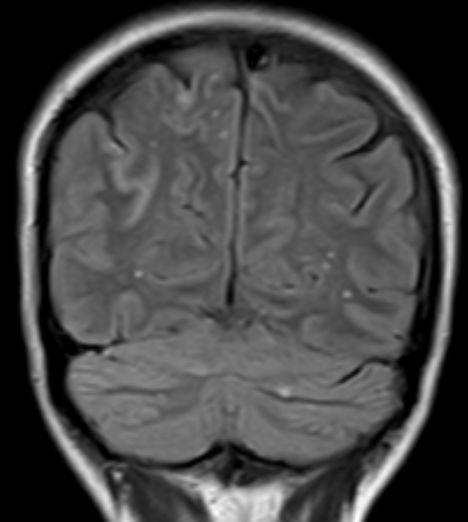

| MRT: multiple Hirnmetastasen | 70-jähriger Mann, der vor einem Jahr ein Adenokarzinom des rechten Lungenmittellappens hatte. MRT-Untersuchung des Hirns, T1-Sequenz mit Kontrastmittel. Klinisch keine Symptome! | |||